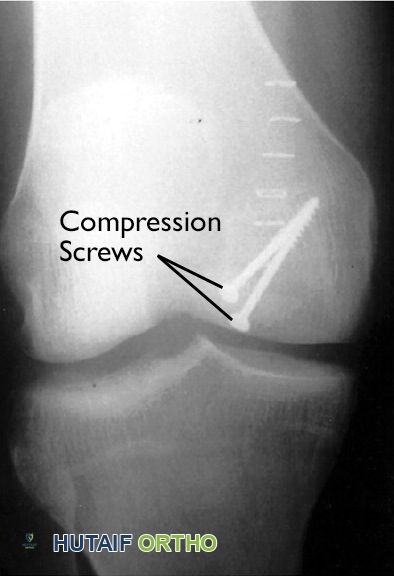

التثبيت الداخلي للآفة

إذا كانت الآفة قد بدأت في الانفصال ولكنها لا تزال في مكانها، يمكن للجراح تثبيتها في مكانها باستخدام أدوات تثبيت داخلية مثل المسامير أو البراغي (المصنوعة عادةً من المعدن أو مواد قابلة للامتصاص). الهدف هو إعادة تثبيت الجزء المنفصل للسماح له بالالتئام والاندماج مع العظم الأصلي.

في هذه الأشعة السينية للركبة، تم تثبيت آفة التهاب العظم والغضروف السالخ في مكانها بمسامير.

*مُعاد إنتاجه بإذن من Crawford DC, Safran MR: Osteochondritis dissecans of the knee. J Am Acad Orthop Surg 2006; 14: